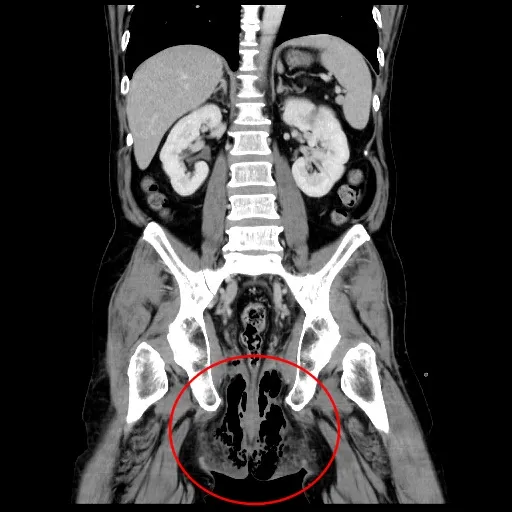

醫師檢查時外觀沒有紅腫跡象,先行給藥建議返家觀察,不料兩天後症狀加劇再度就醫,不僅肛門周邊開始紅腫,甚至延著筋膜一路延伸到陰囊、會陰及前腹壁等部位,立即安排斷層掃描及手指內診,確認是細菌感染所引發的壞死性筋膜炎,也稱為「佛尼爾氏壞死症」,若不緊急執行清創手術,死亡率恐高達9成以上,即使妥善治療,死亡率平均仍介於20至30%,是十分嚴重的急症之一。

檢查發現老翁肛門、陰囊、會陰及前腹壁等部位,被細菌感染引發壞死性筋膜炎。院方提供